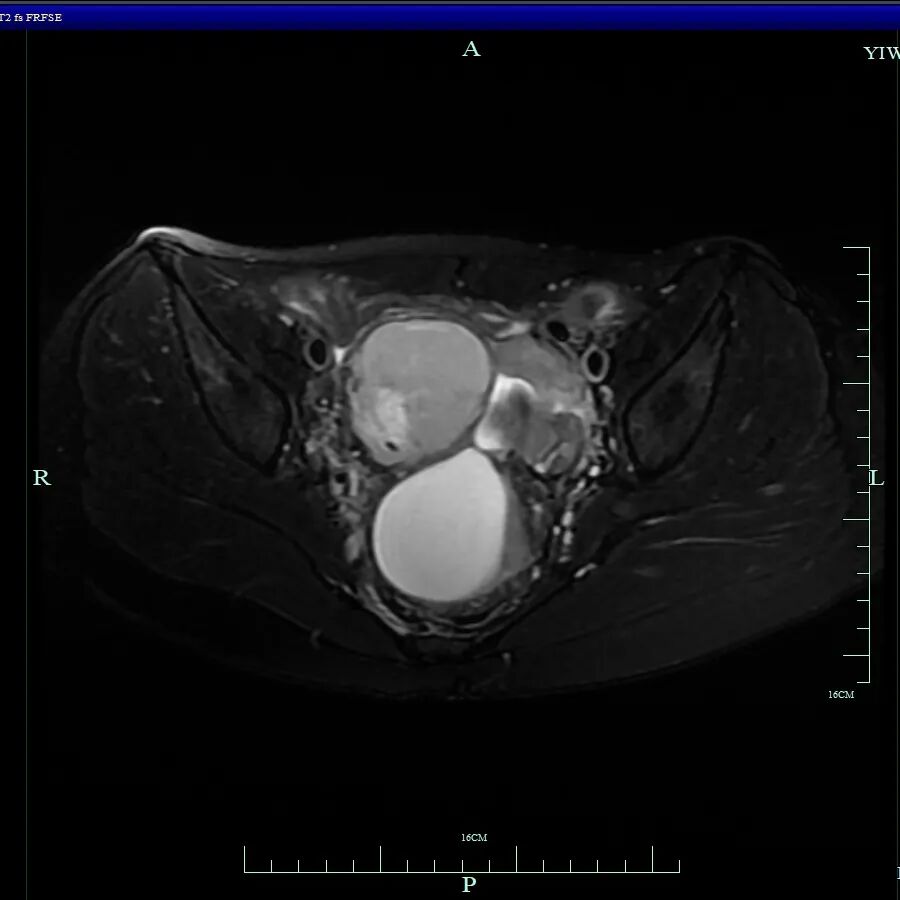

经过紧急CT检查,结果显示小杨的盆腔偏右侧存在一个不明占位。这个结果如同一记警钟,她被迅速转入妇科进一步诊治。

妇科主任吴萍为其详细检查后,诊断为卵巢子宫内膜异位囊肿、子宫内膜异位症四期(重度)、子宫腺肌病、肠道子宫内膜异位症

术中发现其盆腔内器官广泛严重粘连,右侧卵巢有直径约10厘米的囊肿,左侧卵巢亦有囊肿,并在直肠前壁等多处发现异位病灶。手术团队凭借精湛技术成功分离粘连,精准切除了所有病灶,并修复受损组织,保住了生育器官,手术圆满完成。